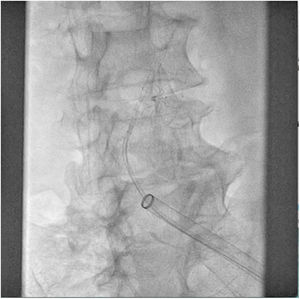

El paciente se traslada a la sala de hemodinamia donde se intenta la extracción del dispositivo. Se utilizan diferentes catéteres lazo de 10, 25 y 30 mm, así como lazos de fabricación con guías largas y cortas intentando movilizar el dispositivo desde diferentes accesos vasculares (acceso bifemoral 6 y 18 Fr y radial 6 Fr) (figuras de la 1 a la 4). Se produce como complicación disección de aorta abdominal con extensión a arteria ilíaca común derecha (figuras 5 y 6) y pérdida total del flujo en extremidad inferior ipsilateral con signos y síntomas de isquemia arterial aguda, por lo que el paciente es trasladado de forma urgente al quirófano de angiología y cirugía vascular. Se realiza disección de aorta abdominal infrarrenal vía laparotomía media con aortotomía longitudinal en el lugar de la localización del cuerpo extraño visualizándose el dispositivo migrado anclado a la íntima-media de la pared arterial. Se procede a su extracción y posteriormente se realiza cierre de aortotomía con parche de pericardio bovino fijando la disección y corrigiendo así el defecto (figuras de la 7 a la 9). El paciente sale de quirófano con pulso pedio bilateral y excelente perfusión distal.